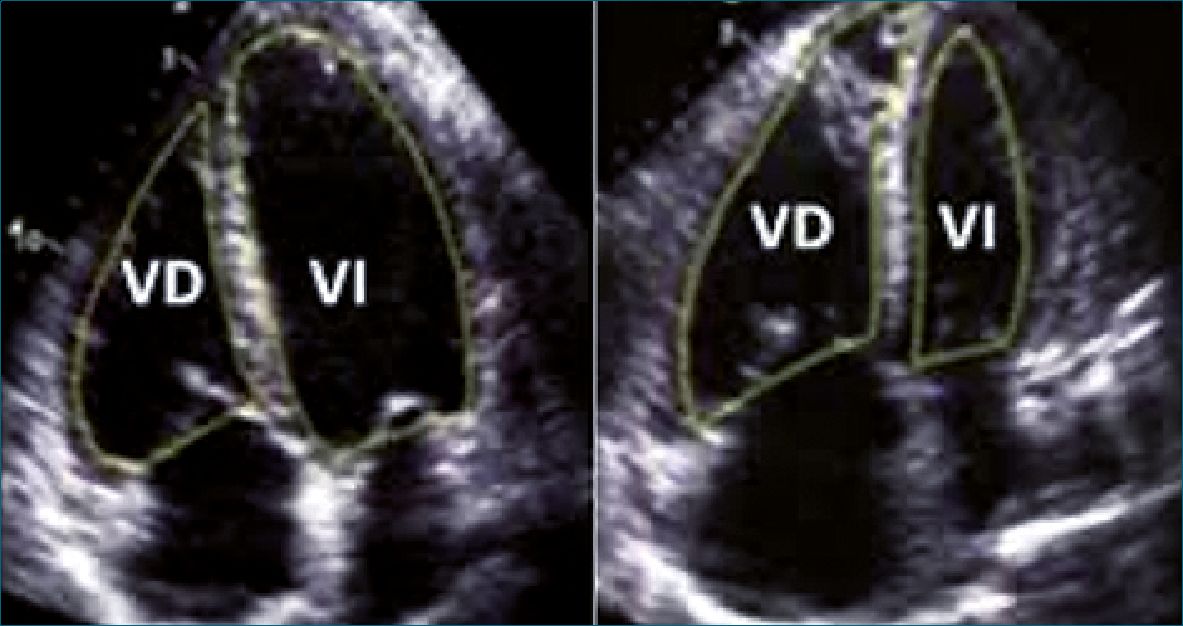

Para evaluar la función del ventrículo derecho (VD), el anestesiólogo deberá obtener una visión en A4CH, en la cual una relación VD/VI > 0,6 en niños mayores y > 1 en lactantes y neonatos (Figura 6), sugiere disfunción del VD.

Figura 6. A la izquierda relación VD/VI > 0,6 en niños mayores; a la derecha relación VD/VI >1 en lactantes[19],[20].